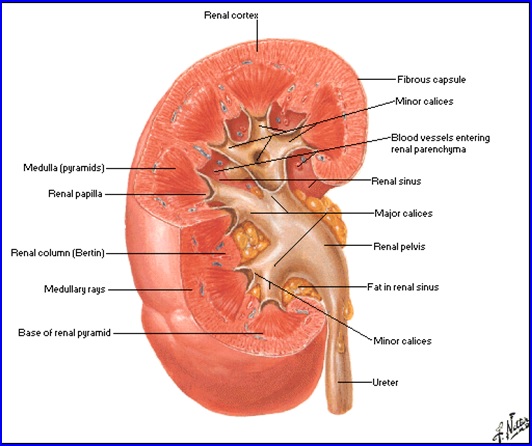

Rinichiul

Organ retroperitoneal, pereche şi simetric, cu formă asemănătoare bobului de fasole.

Dimensiuni şi greutate: depind de statura individului, vârstă, sex şi sunt în medie 12/6/3,5 cm; 140-170g.

Situaţie: de o parte şi alta a coloanei vertebrale, corespunzând vertebrelor T11-T12 superior şi L2-L3 inferior, de-a lungul marginii laterale a m. psoas. Prezenţa ficatului pe partea dreaptă face ca rinichiul drept să fie situat mai jos faţă de cel stâng.

Structură:

- Capsulă fibroasă; grăsime perirenală; fascia renală (Gerota); grăsime paranefretică.

- Sinus renal - elementele pediculului renal.

- Parenchim:

- corticala renală (1,2-1,5 cm grosime; conţine glomerulii renali şi segmente din tubii uriniferi);

- medulara (formată din 8-12 piramide renale).

Sistemul pielo-caliceal

- Calicele minore, în număr de 8-12, drenează fiecare câte o piramidă renală

- Interfaţa dintre piramidă şi calice = paplila renală.

- Calicele minore se unesc pentru a forma 2-3 calice majore care se unesc şi formează bazinetul renal.

- Raporturi anatomice ale bazinetului:

- Intrarenal: ultimul plan al pediculului renal: aretera, vena.

- Extrarenal:

- posterior: m. ilio-psoas;

- anterior dreapta: duodenul 2, vena cava inferioara;

- anterior stganga: corp pancreas.